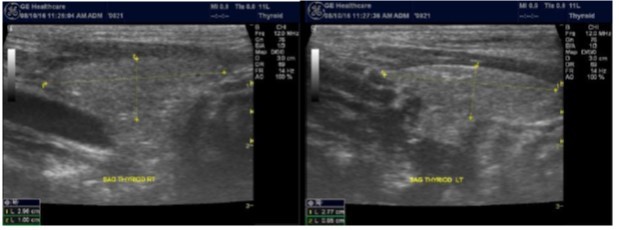

The superficial location of the thyroid gland renders it ideal for ultrasound examination 8. High resolution grey scale images can easily be obtained using high frequency transducer. In the transverse view, normal thyroid gland has the butter fly appearance, with left and right lobes connected with a narrow isthmus, Figure 1A. Both lobes can be imaged separately in the longitudinal plan, Figure 1B

Figure 1A.Normal thyroid gland transverse view

The main objective of this study is to examine the morphological and functional abnormalities of the thyroid gland among ESKD Patients. To achieve this objective, all the 92 chronic hemodialysis patients at Prince Sultan Kidney Dialysis Center at Alqunfudah general hospital were consented and included in the study. All patients underwent thyroid ultrasound scanning. Grey scale imagings were obtained first followed by Doppler interrogations. GE ultrasound system with high-resolution linear probe (7.5-12 MHz) and advanced scanning techniques like extended field of view and compound harmonic imaging were applied to get the best image quality. Demographic and clinical data were recorded for all patients in addition to chemical and hormonal laboratory results. The collected data was processed and analyzed to satisfy the objectives of the study. The categorical data was presented as frequency and percent. The continuous data was presented in terms of mean and standard deviation. X2 test was used for categorical data, student t-test was used for continuous data. To better study the relationship between the dependant and the independent variables, logistic regression was used to study all the possible directions of the association between the dependant and the independent variables.